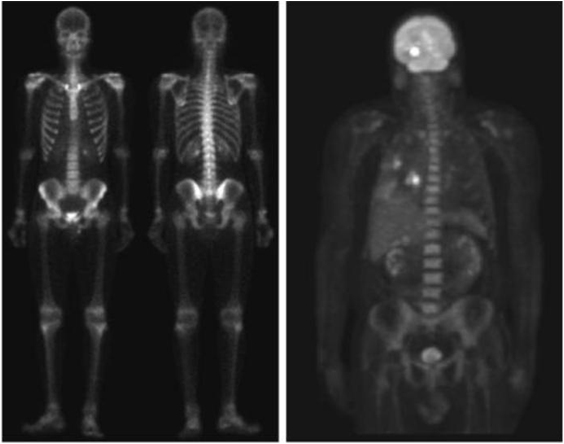

Imaging in the radio band

• 주요 응용분야: 의학(MRI: magnetic resonance image), 천문학

Image

인체의 MRI 무릎, 척추

게자리 (pulsar)